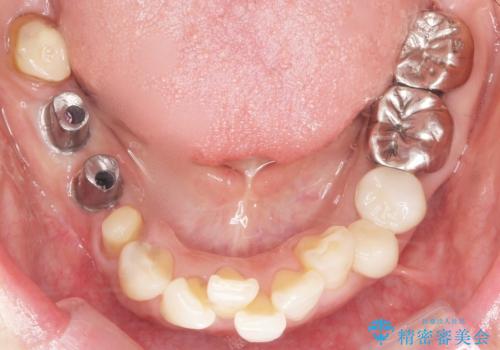

- 奥歯のインプラントをご希望され、来院された患者様です。

骨が薄いため、他院ではインプラントできないと言われたとの事でした。

精査したところ、右下4の根尖病変及び右下5の欠損を認め、右下6は残根となり保存不可能な状態でした。

保存不可能な歯を抜去後、インプラント治療と根管治療を行いました。